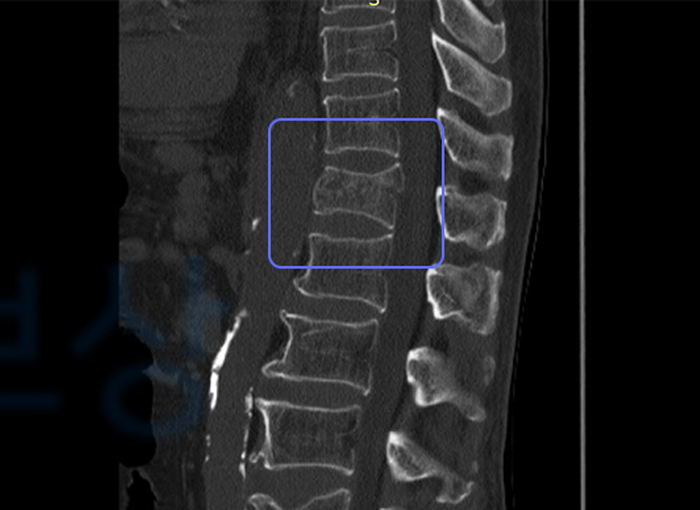

T12 부위의 골절, 폐쇄성 (S22070)

병원에 내원하여 진단 결과 두개골과 흉추 12번 골절되셨는데요. 척추체 중에 흉추 12번과 요추 1번은 허리에서 하중을 가장 많이 받아서 낙상사고 시 제일 흔하게 압박골절이 발생하고는 합니다.